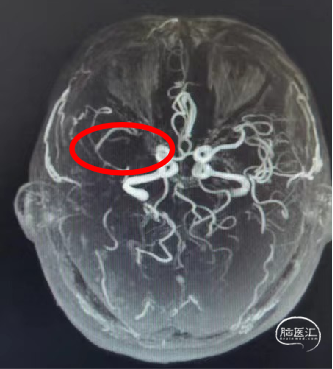

颅脑MRA(外院1月前):右侧大脑中动脉未见显影,考虑闭塞。

DSA提示:右侧大脑中动脉M1起始部极重度狭窄、次全闭塞,狭窄远端M1段管径约2.1mm,近端颈内动脉末端管径约3.3mm;M2段主干中度狭窄,分水岭下移;颈内动脉入路非常迂曲。